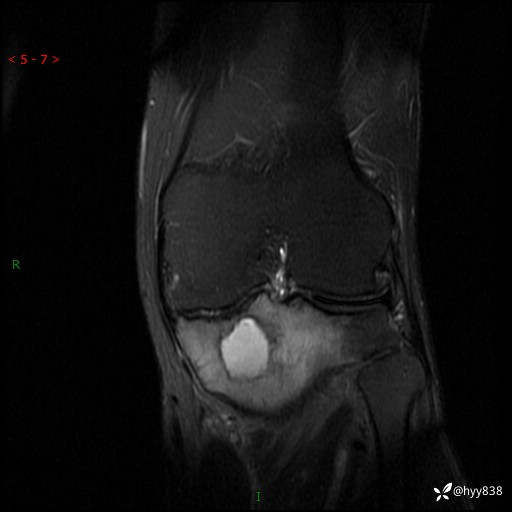

cor T2WIfs